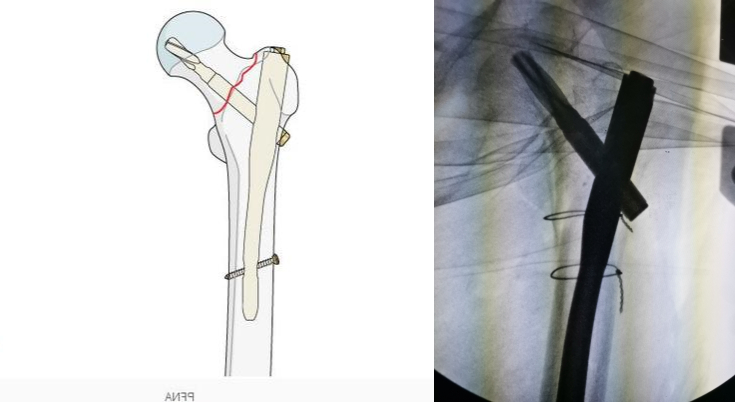

手术首先切开皮肤,严重粉碎的股骨粗隆间骨折可以进行钢丝固定,这一步对于简单的骨折可以省略。该患者骨折粉碎,移位明显,必须进行钢丝的固定,在钢丝固定后我们欣喜地发现骨折已经完全复位:

钢丝固定

在完全复位后就可以进行髓内钉内固定的操作,我们将髓内钉插入骨髓腔,对骨折断端进行固定:

髓内钉